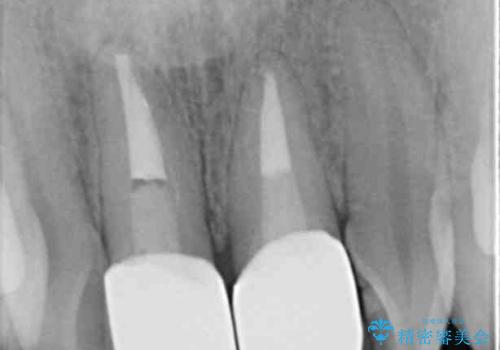

- 前歯の変色とガタつきがきになるとのことで来院されました。

矯正治療の希望はなかったため、セラミッククラウンで被せて治療していくことになりました。

元々根管治療がされていたにも関わらず被せ物が作られておらず、このままではどんどん変色が進んでいってしまう状態でした。

歯をある程度削ることにはなりますが、被せ物にすることで歯の変色を隠し短期間でキレイな口元に仕上げることができました。